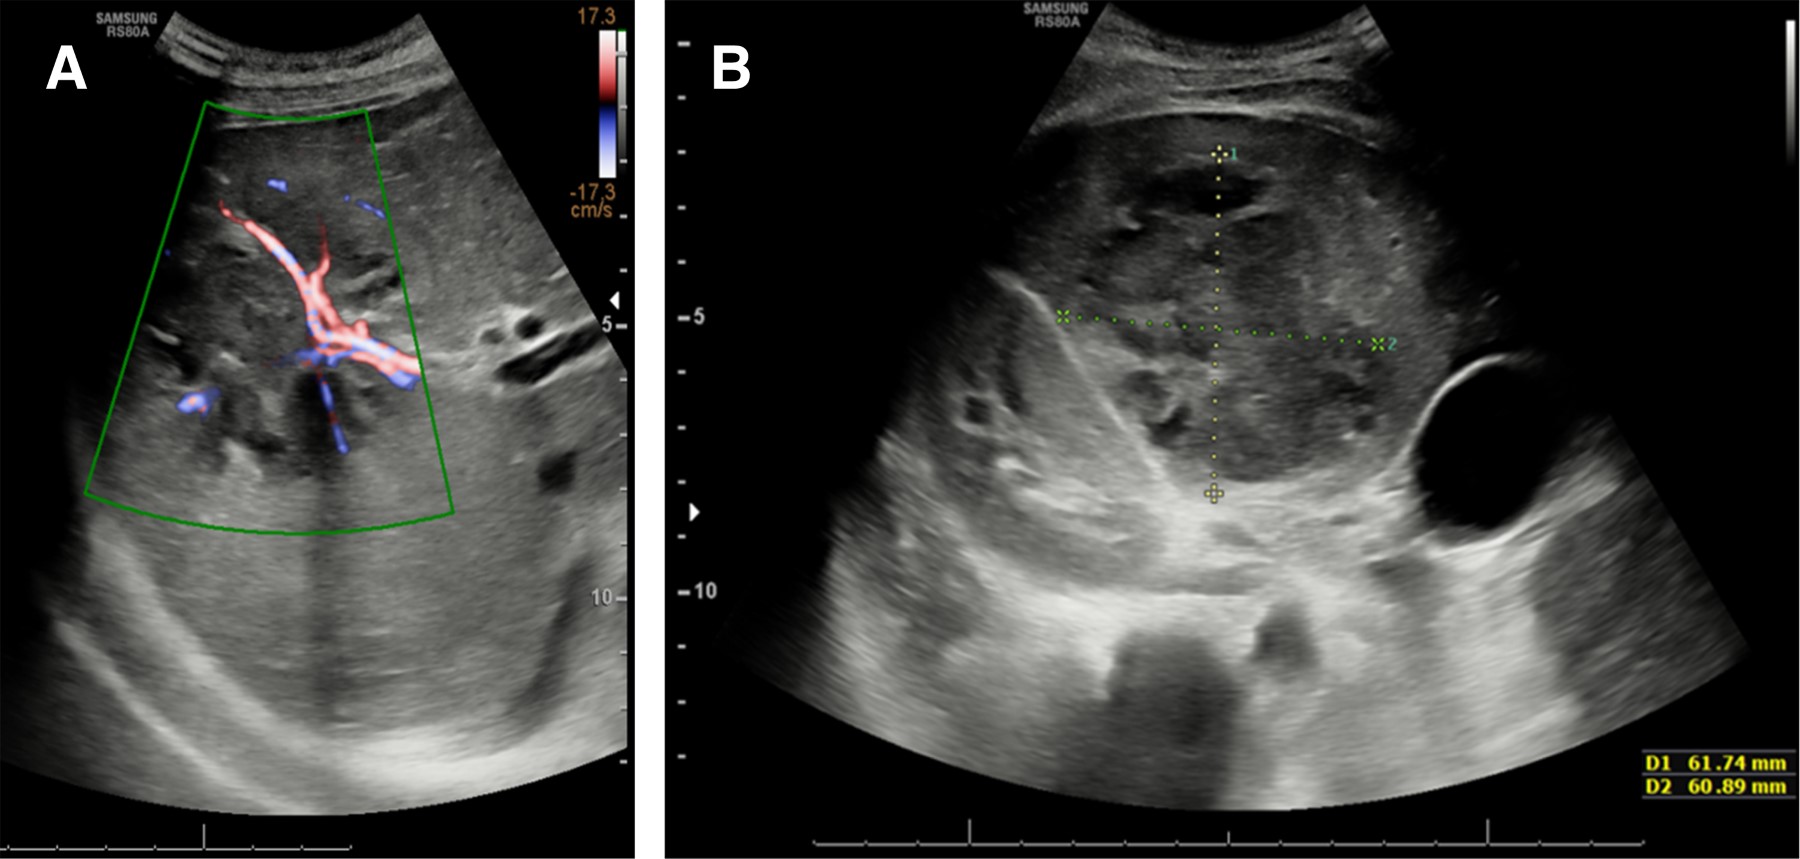

Se realizó una resonancia magnética abdominal (Figura 2) y se confirmó la lesión en lóbulo hepático derecho de 6 × 7 centímetros, hiperintensa de manera homogénea en T2, que restringía a la difusión y realzaba en la periferia con la administración de contraste intravenoso en T1 compatible con absceso hepático.

La ecografía es el estudio de imagen inicial de elección, con una alta sensibilidad (80-95%); además, permite descartar enfermedad biliar asociada. La tomografía axial computarizada es la prueba de imagen de mayor sensibilidad (97-100%). Sin embargo, últimamente se está postulando la resonancia magnética como prueba de elección, ya que permite realizar el diagnóstico diferencial entre distintos tipos de lesiones hepáticas, descartar la presencia de lesiones en otras localizaciones y definir anatómicamente la lesión con exactitud. Característicamente, los abscesos hepáticos son hipointensos en T1, hiperintensos en T2, captan gadolinio de manera perilesional en T1 y restringen a la difusión.17